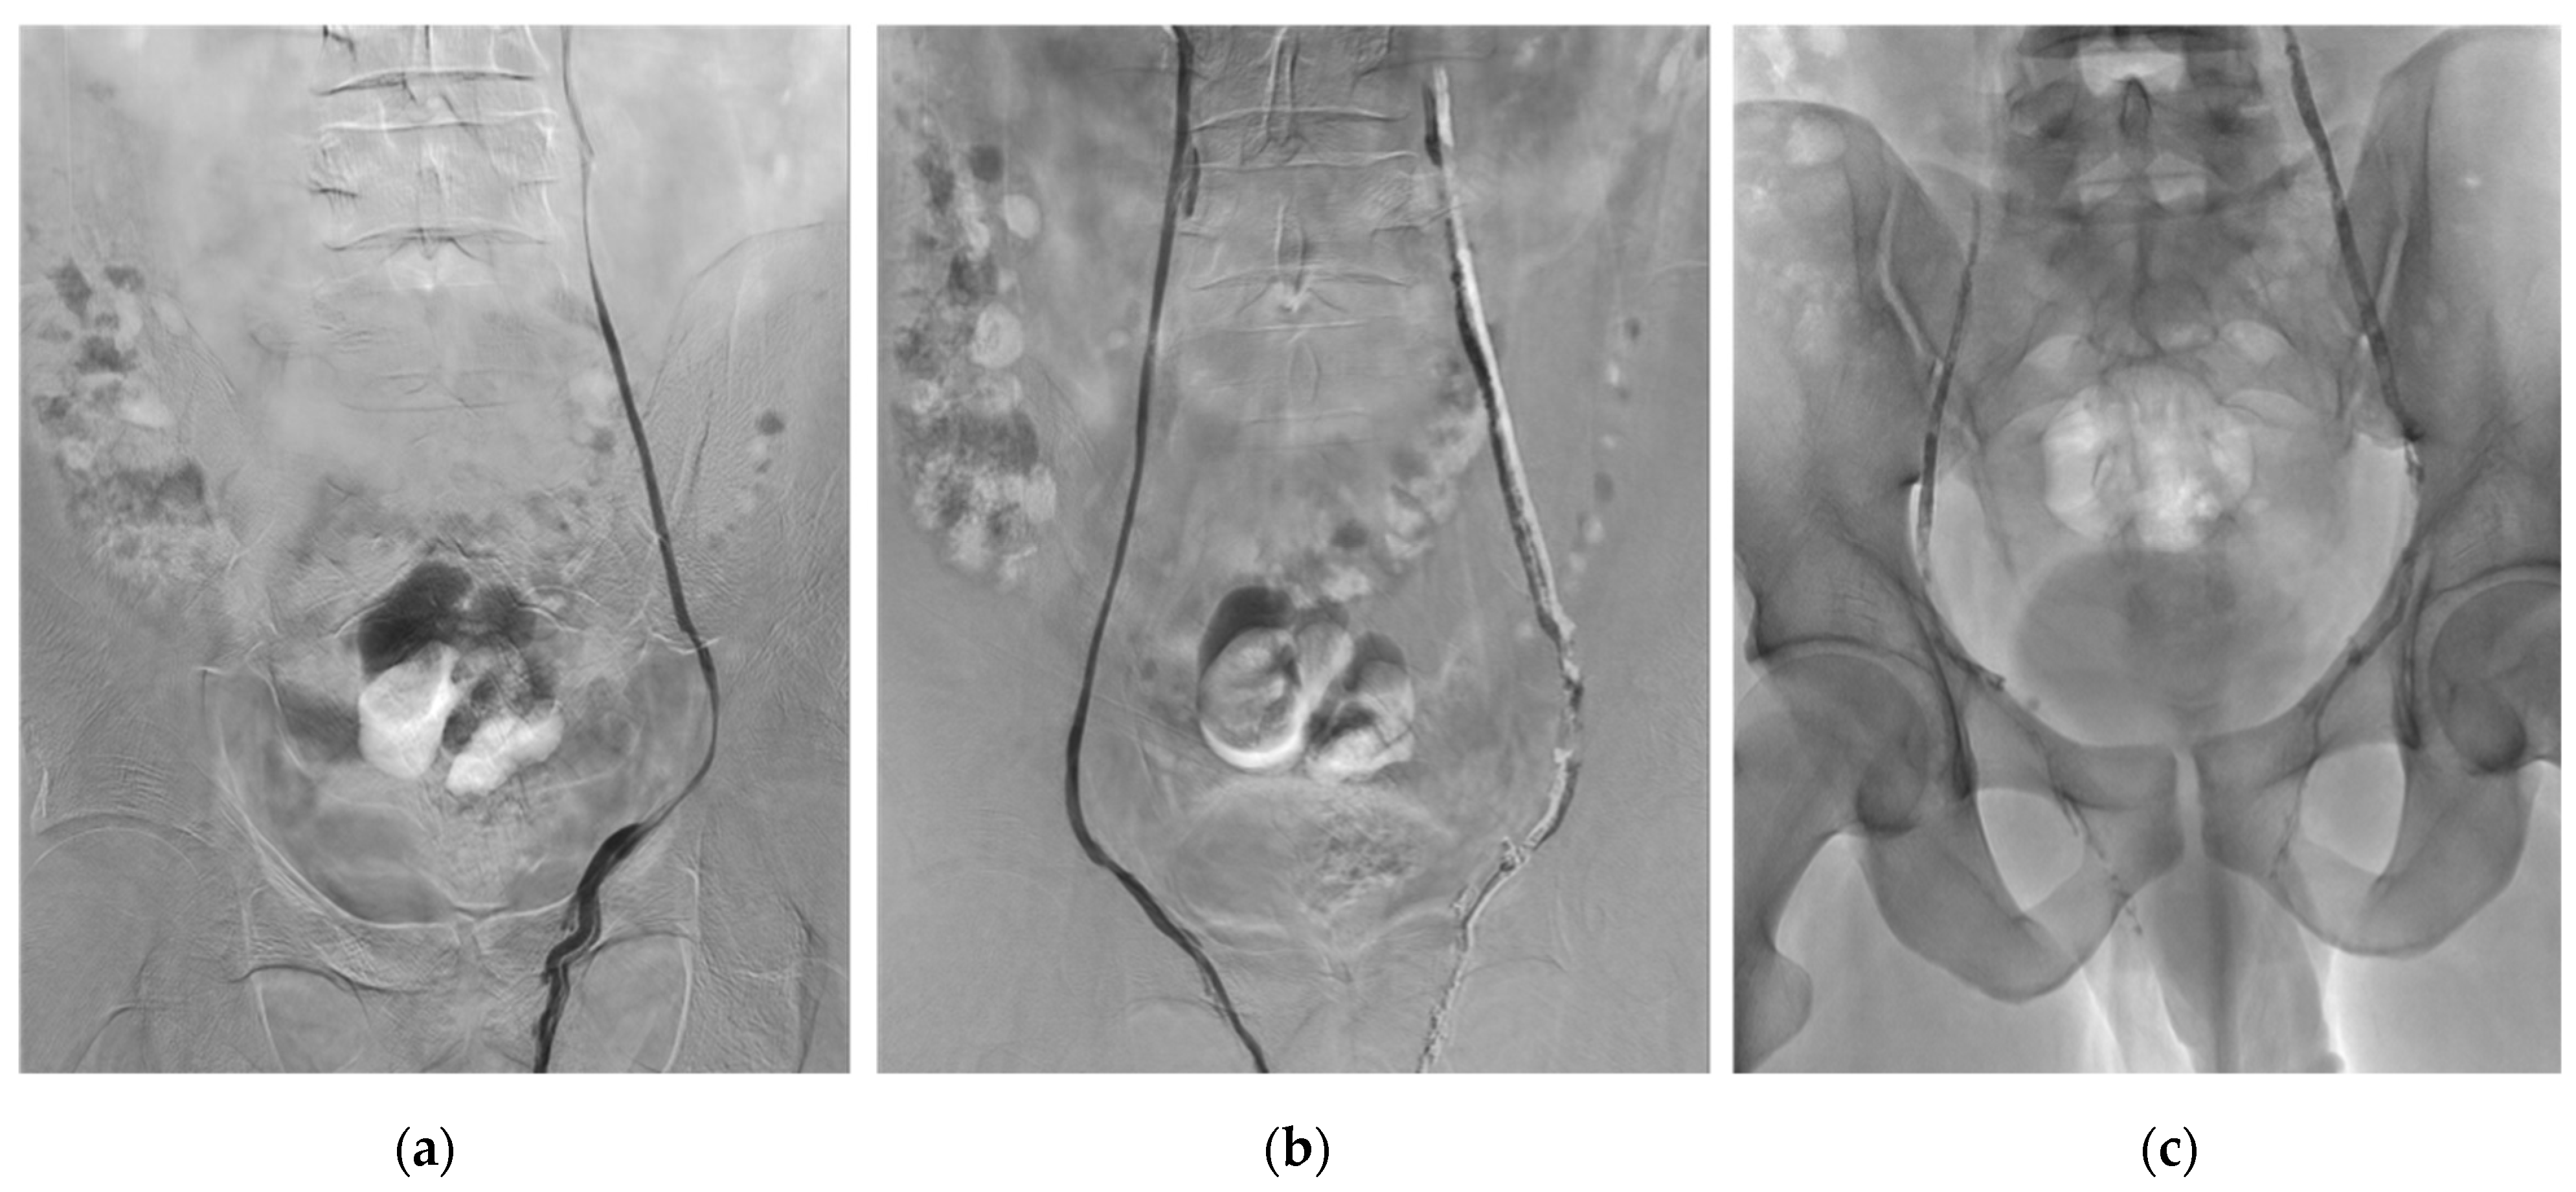

Figure 1 shows an example of bilateral VE procedure using Glubran®2.

Figure 1.

Example of typical bilateral varicocele embolization (VE) procedure using NBCA-MS Glubran®2. (a) Left gonadal vein venography through a 5-French Cobra catheter by transvenous femoral approach. (b) Right gonadal vein venography after VE of the left gonadal vein using Glubran®2-Lipiodol® mixture at a 1:1 ratio. (c) Plain X-ray image after bilateral VE using Glubran®2-Lipiodol® mixture at a 1:1 ratio. In more detail, a microcatheter is placed below the iliopectinal line and the dead space is filled with 5% dextrose solution to avoid intracatheter glue polymerization. The embolization procedure is then performed using glue mixed with Lipiodol at a ratio of 1:1. Glue–Lipiodol mixture is then injected under strict fluoroscopic guidance, with continuous injection performed manually and a display of real-time distribution. The glue injection begins in the distal intrapelvic segment of the gonadal vein, and the catheter is withdrawn slowly while injecting NBCA-MS under fluoroscopy. Injection is then stopped before the pampiniform plexus is reached. The microcatheter is then removed when the glue fills the venous space selected beforehand. Here we can see the cast of glue along the left and right gonadal veins after embolization.